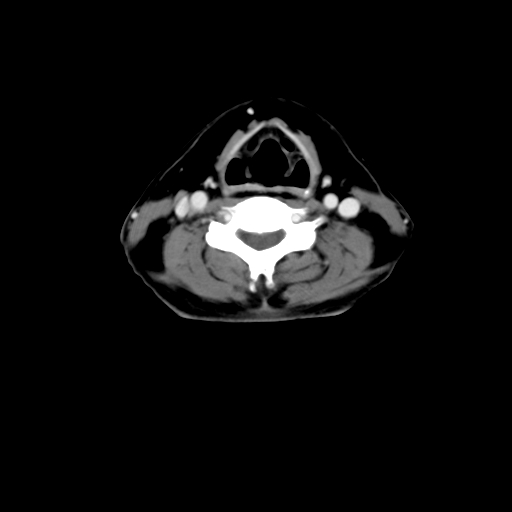

标题: CT24019:男,45岁,发现颈部肿物5个月。 [打印本页]

男,45岁,发现颈部肿物5个月,彩超示:双侧颈部及下颌部软组织增厚。

考虑双侧颈项部良性对称性脂肪增多症。